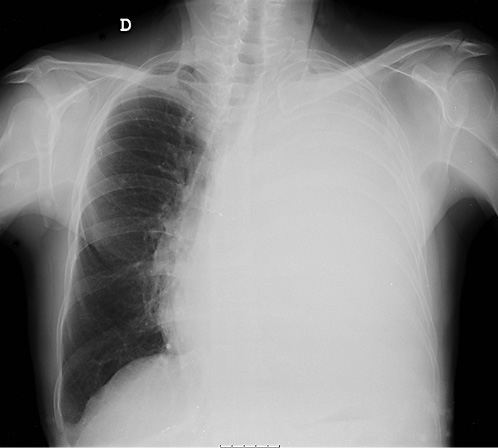

On ERCP, the Wirsungogram identified a point of ductal leak-age in the body of the pancreas, with contrast spreading to the middle of the column (most likely to the pseudocyst lumen) (Fig. 3). Pancreatic sphincterotomy and placement of a double-flanged straight 5-Fr plastic stent with 9 cm (the longest one avail-able in the unit) in the duct of Wirsung, up to the ductal disruption site (Fig. 4), were performed.

Fig. 4 Radiograph showing the pancreatic plastic stent after endoscopic retrograde cholangiopancreatography.